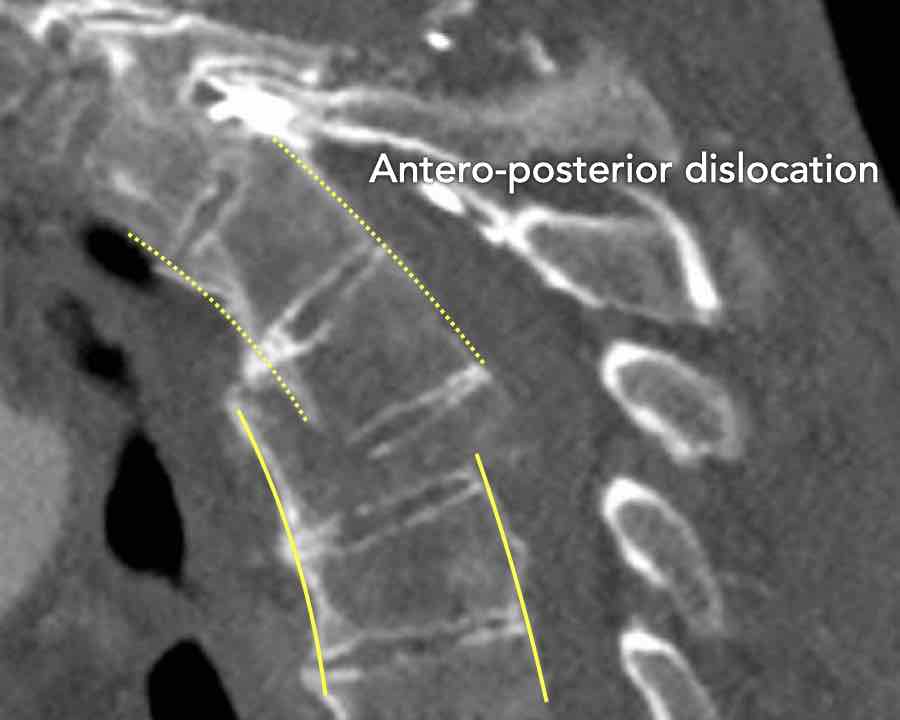

Scroll through the images

Findings:

- Perched facet joints (yellow curved arrows), so think of C injury.

- Posterior displacement of the vertebral bodies in the midline.

- Secondary A4 injury of the vertebral body.

Conclusion

Type C + A4 injury